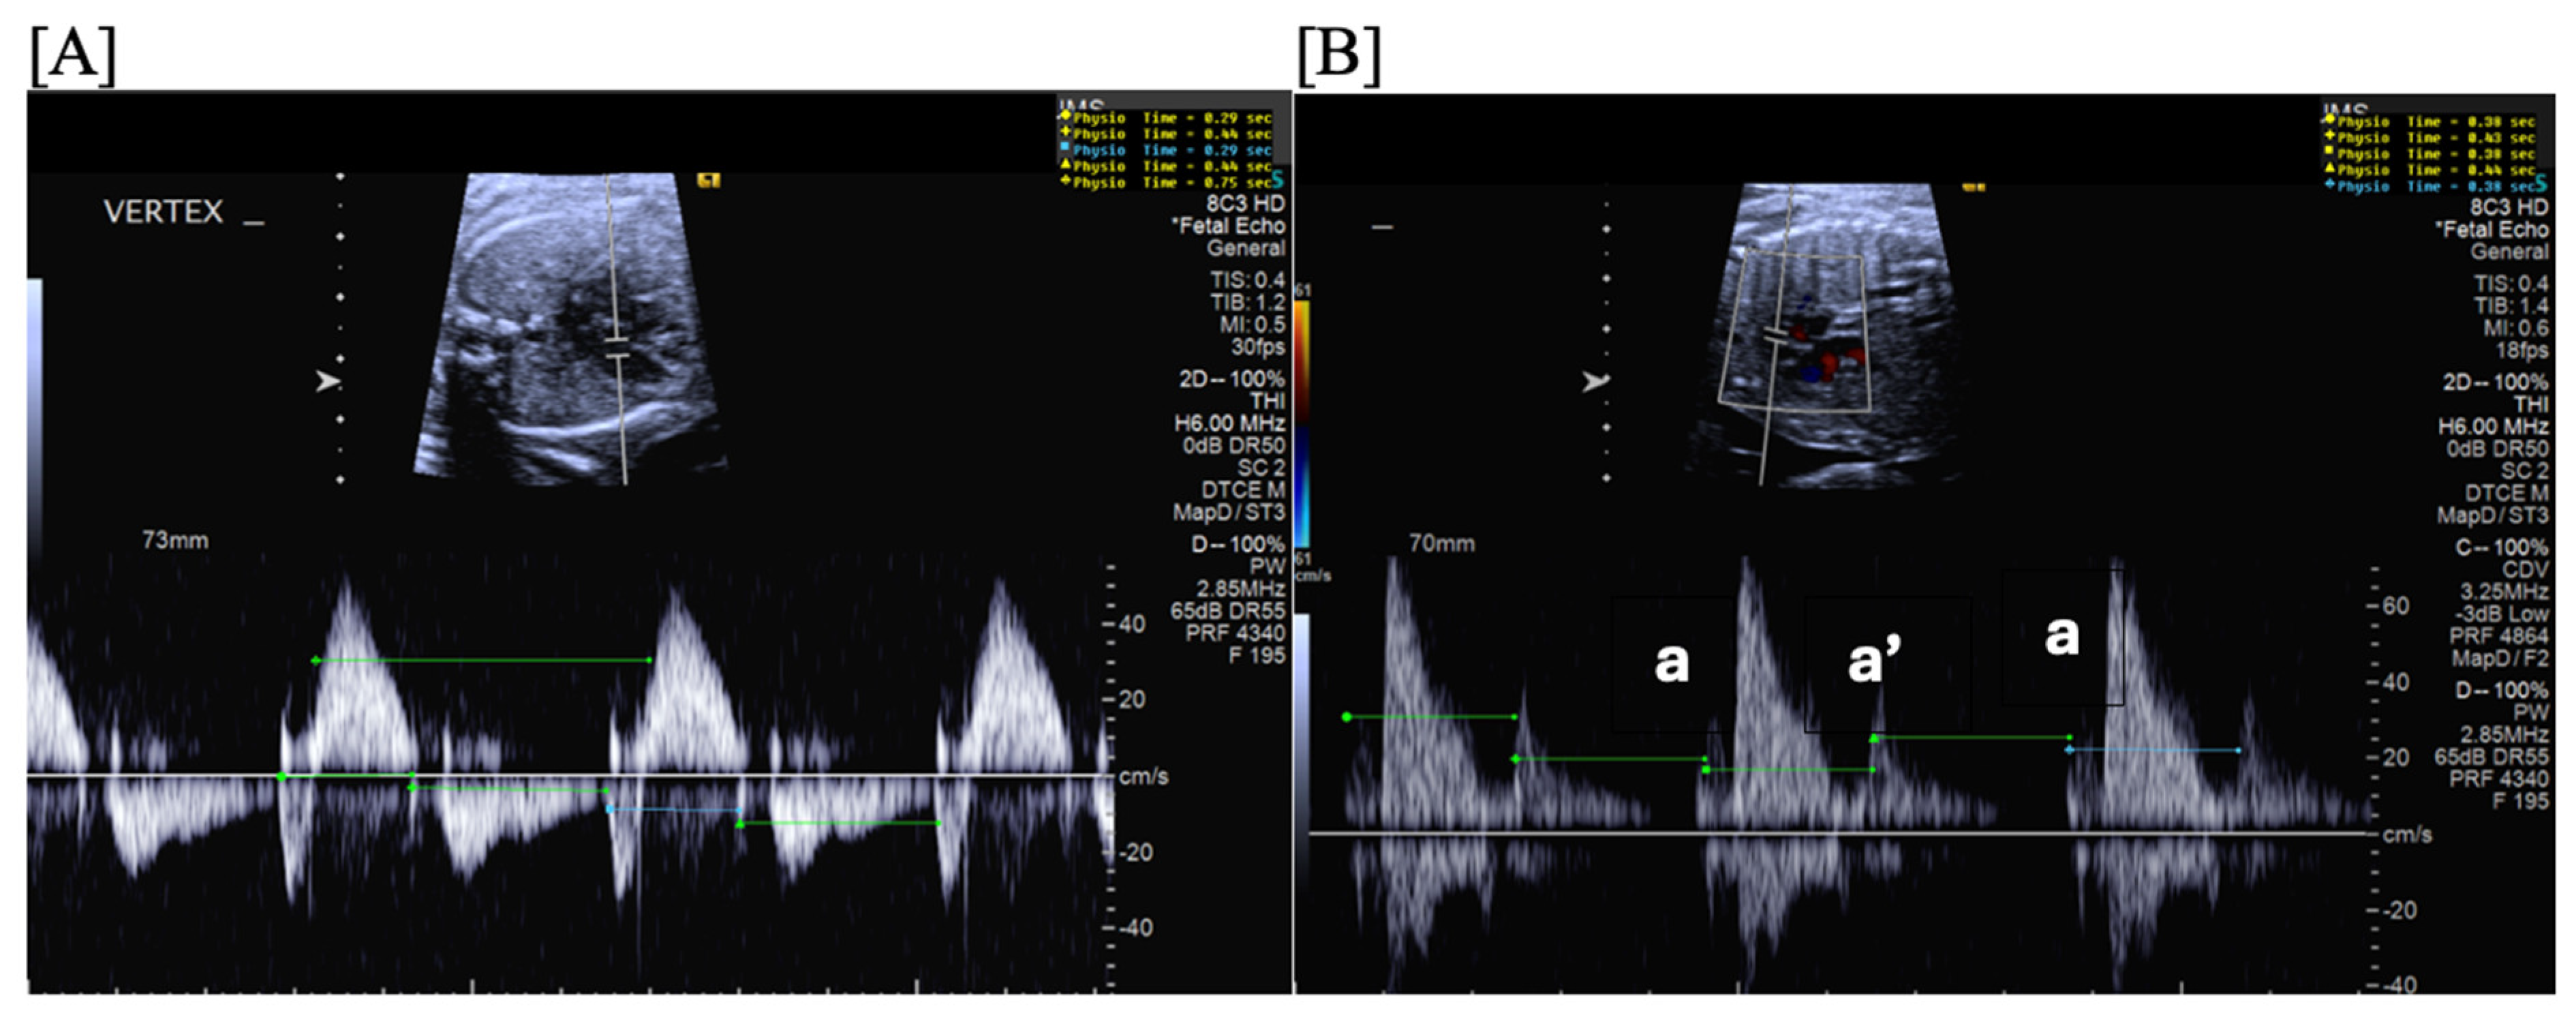

- Short VA SVT (Figure 3 and Figure 4) demonstrates a ventricular–atrial (VA) interval that is less than half of the ventricular–ventricular (VV) interval (VA:AV ratio < 1) and a sudden onset and termination of tachycardia; tachycardia usually terminates with a non-conducted atrial contraction. Short VA SVT includes AVRT (also known as orthodromic reciprocating tachycardia, ORT) and atrioventricular nodal reentrant tachycardia (AVNRT). Short VA SVT typically presents after 18 weeks of gestation.

- Long VA SVT (Figure 4) demonstrates a VA interval that is more than half of the VV interval (VA:AV ratio > 1). Long VA SVT includes EAT and PJRT. A distinguishing feature of EAT is tachycardia termination with ventricular contraction. Long VA SVT may occur as early as 12 weeks of gestation. Because long VA tachycardias have slower rates, they are less likely to cause hydrops.